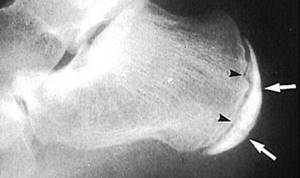

- Рентгеновская диагностика. При болезни Шинца на снимке будет наблюдаться пятнистость паточной кости и отсутствие гомогенности тени ее бугра. В некоторых случаях возможно наличий отложения солей, которые видны как небольшие островки.

При тяжелых формах заболевания отчетливо просматриваются такие рентгенологические признаки как отделение фрагментов краевой кости и увеличение расстояния между пяточной костью и апофизом.

Диагноз болезнь Шинца выставляется специалистом-ортопедом с учетом анамнеза, клинической картины и рентгенологических признаков. Наиболее информативен снимок в боковой проекции.

Рентгенография пяточной кости на 1 стадии заболевания свидетельствует об уплотнении бугра, расширении щели между бугром и собственно пяточной костью.

Выявляется также пятнистость и неравномерность структуры ядра окостенения, участки разрыхления кости и коркового вещества и смещенные в сторону от центра секвестроподобные тени.

На поздних стадиях на рентгенограммах видны фрагменты бугра, а затем признаки перестройки и формирования нового губчатого вещества кости.

В норме пяточный бугор может иметь до четырех ядер окостенения, что часто затрудняет рентгендиагностику.